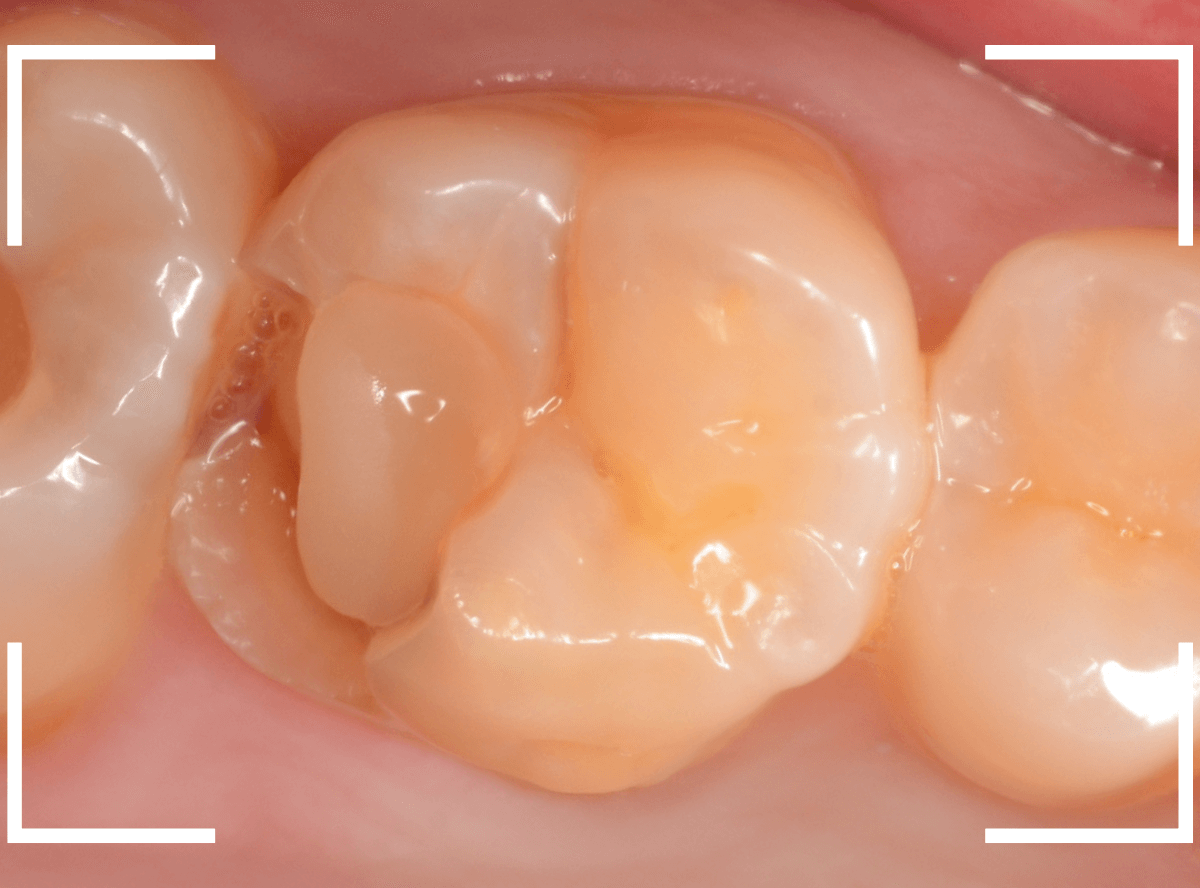

直近の患者さんの例で説明しましょう。

3本の大きな虫歯を除去した後に、ベースセメントで歯を保護します。

ここでこのまま、つめものが入るように歯をトリミングして型どりをしてもいいのですが、症状が出ないかしばらく経過観察します。

症状がないのを確認できたら、改めて歯のトリミングをして型どりをして、つめものをsetします。